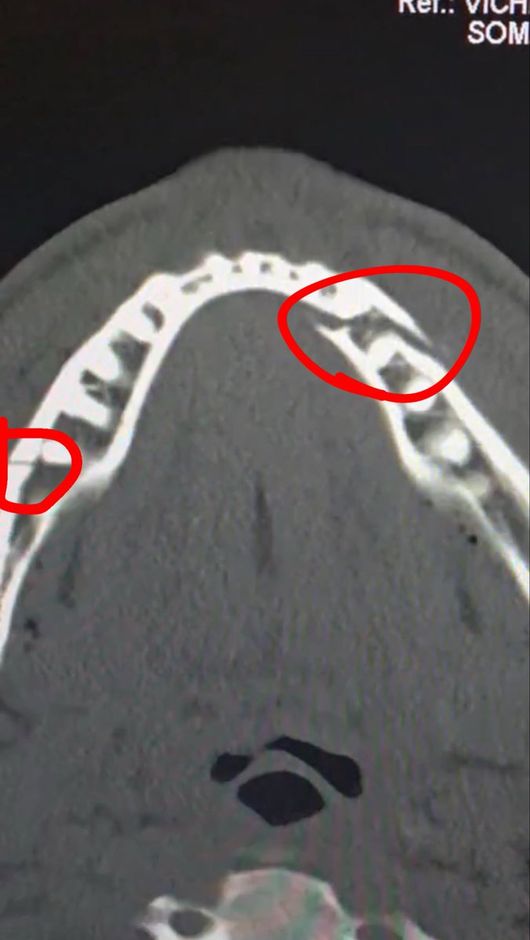

폴의 부상도 심각했다. 진단 결과 그의 턱뼈는 두 곳이나 골절돼 세 동강이 난 모습이었다. 그는 곧바로 수술대에 올랐고, 티타늄 플레이트 두 개를 삽입했다. 치아도 일부 제거해 한동안 정상적인 식사도 할 수 없었다.

이후 폴은 자신의 수술 후 상태를 공개하면서 "통증이 심하지만 난 괜찮다. 턱뼈가 두 군데나 으스러졌다. 7일 동안 유동식을 먹어야 한다"라고 밝혔다. 경기를 앞두고 조슈아에게 "널 죽여버리겠다"라고 도발했던 폴이지만, 조슈아의 벽은 너무나 높았다.